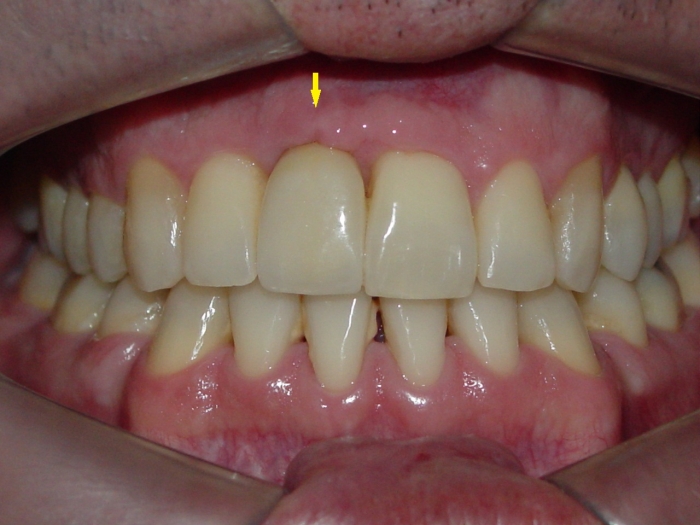

Imagens do caso com prótese fixa em porcelana

Sorriso final, do caso terminado em julho de 2012